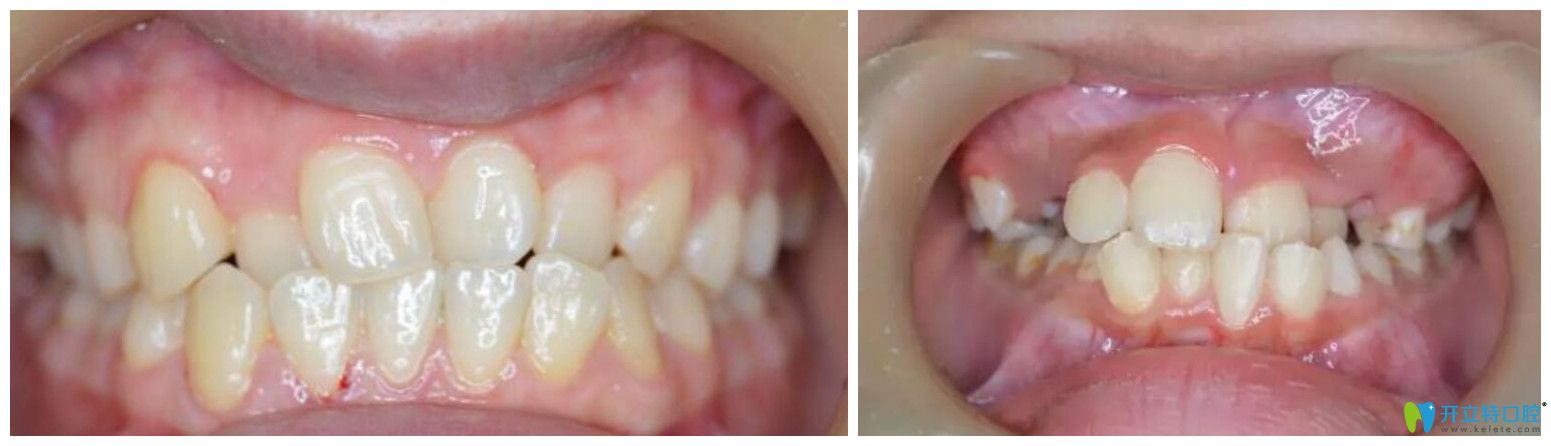

2、個(gè)別牙反合

通常的表現(xiàn)是個(gè)別門牙或兩顆牙反合。會(huì)影響到孩子上面部的正常發(fā)育,可能導(dǎo)致孩子的上唇部凹陷。而且,其潛在的危害是,較有可能導(dǎo)致兒童成長(zhǎng)到3040歲時(shí)出現(xiàn)顳下頜關(guān)節(jié)紊亂病。

個(gè)別牙反合